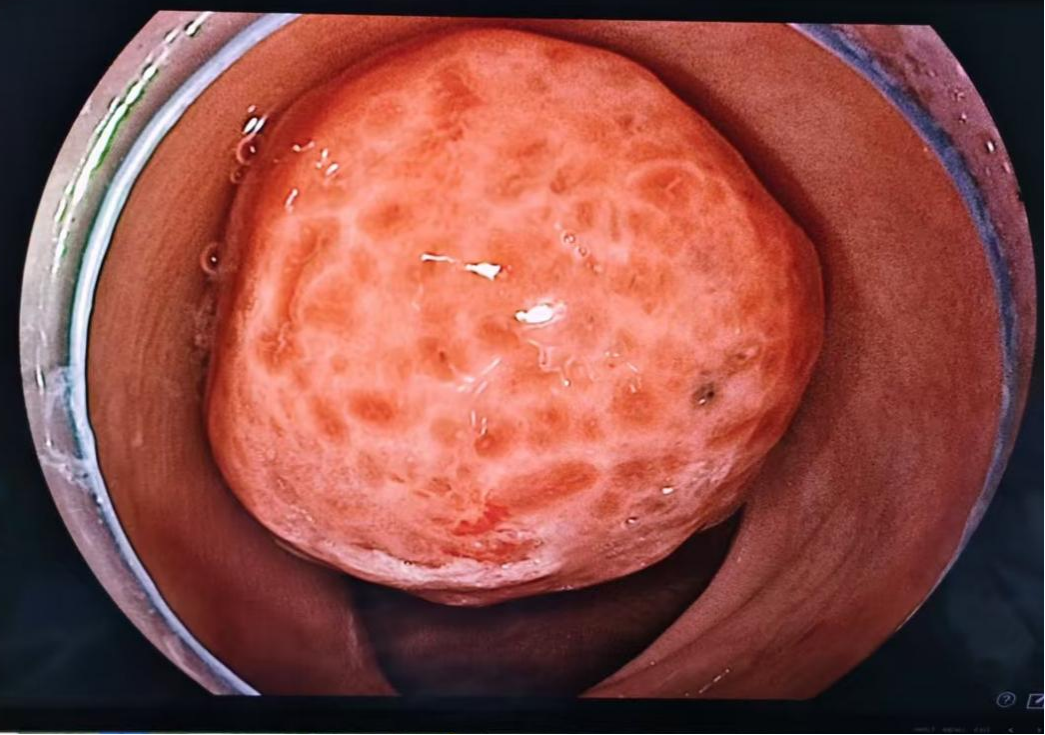

在儿童医学中心、消化内科及麻醉科的多学科协作下,消化内科党支部书记兼内镜中心副主任滕贵根在内镜护士王依晗、孙学信的默契配合下为患儿行巨大息肉切除术,鉴于该息肉体积巨大(占据肠腔约3/4),采用"尼龙圈结扎+止血夹封闭"的双保险手术方案,手术顺利完成,术后创面愈合良好,未再出现便血等不适。

图1 内镜下息肉